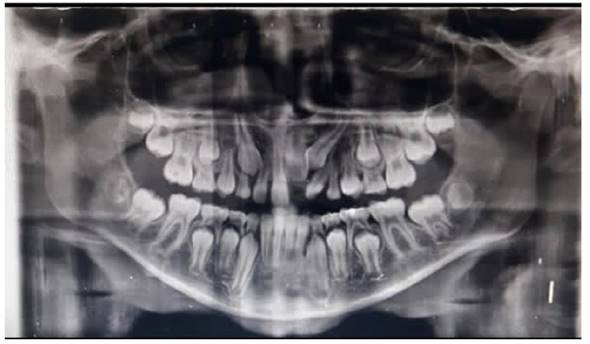

Al examen clínico inicial (Figura 1), se aprecia ausencia de unidad dentaria superior; y al examen radiográfico inicial (Figura 2), la radiografía panorámica muestra una falta de erupción del incisivo central superior izquierdo permanente (UD 21), con desviación hacia el mesial de canino superior izquierdo permanente (UD 23) sin erupcionar, en íntimo contacto con la raíz del incisivo lateral izquierdo permanente (UD 22). Se puede apreciar presencia de zona radiolúcida en tercio incisal de la UD 21, presuntamente asociada a un defecto del desarrollo del esmalte, específicamente hipoplasia de esmalte. Presenta un patrón de exfoliación dental acorde a la edad en el sector inferior, etapa 8 de Nolla.

No se evidencia presencia de dientes supernumerarios ni agenesias dentales. En las imágenes axiales y frontales de la tomografía axial computarizada, puede observarse la falta de erupción de la UD 21 y su estrecha proximidad con la UD 23, así como la dilaceración radicular de la UD 22 (Figura 3). Al examen extraoral, se observa perfil facial ligeramente convexo; y al examen bucal intraoral, se aprecia overjet y overbite normales, sin apiñamiento, líneas medias dentales coincidentes con la línea media facial, clase I molar.